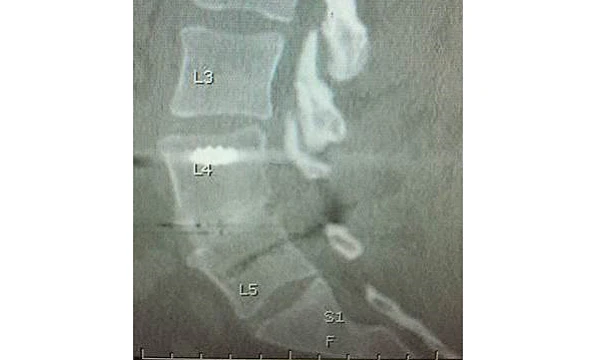

During NASS, Timothy Bassett, MD, of SouthEastern Spine Specialists, Tuscaloosa, AL, presented his ‘Early Clinical Experience with a PEEK-OPTIMA HA Enhanced Device for Lumbar Fusion’. The 1-2 level TLIF (Transforaminal Lumbar Interbody Fusion) procedure utilised the EVOS HA Device, from Cutting Edge Spine, intended for use in skeletally mature patients with Degenerative Disc Disease (DDD) of the lumbar spine, plus autograft bone with posterior instrumentation. No biologics were used in this series of nine patients.

The clinical results were evaluated for pain on the Visual Analogue Scale (VAS), opiate usage, neurological function, re-operations and complications. Fusion results were evaluated using anteroposterior (AP) and lateral X-rays at six weeks and 12 weeks, and a CT scan at six months. Dr Bassett concluded, “Very rapid visible bone fusion occurred in the interbody region in six weeks, according to plain radiographs, with correspondingly good clinical results including no neurologic consequences beyond 6 weeks, no implant migrations, no subsidence, and no pseudoarthroses. More importantly, 9/10 fusions were definitively solid on 6 month CT scan with autograft bone, despite some challenging patients. The one that didn’t show complete fusion was progressing to fusion and used one pack of tobacco daily, both pre- and post-operative, contributing to the fusion challenge.